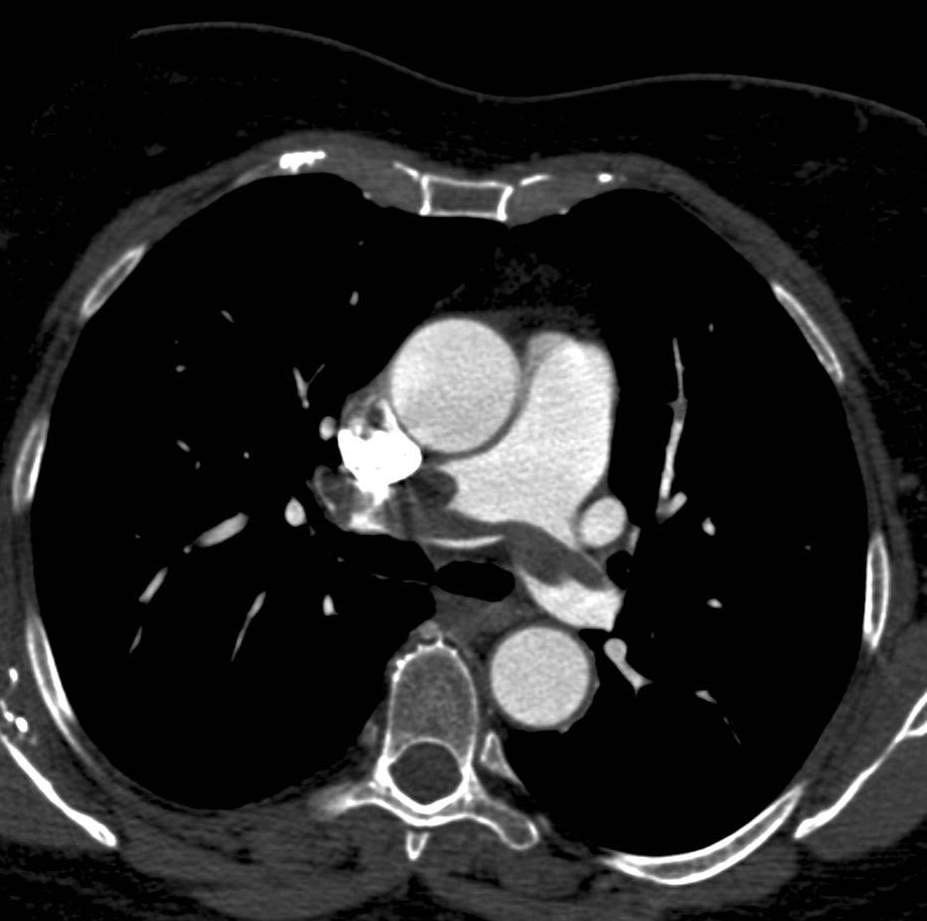

There are two main types of aorta dissection according to the Stanford classification: type “A” when the ascending aorta is involved, and type “B” when the dissection occurs distal to the origin of the left subclavian artery and it does not propagate to the level of ascending aorta or the aortic arch. The two types are distinguished because of their acute complications: type “A” dissection can cause the obstruction of the coronary trunks or, in case of a pericardial rupture, it can cause consequent pericardial tamponade and sudden death. Hence these cases require immediate surgical intervention with a cardiac surgical background. In contrary type “B” dissection can cause the acute obstruction of the abdominal aortic branches and can lead to life threatening conditions only in a subacute manner (intestinal ischemia, renal insufficiency). These conditions can also require surgical intervention (vascular surgery) but they rarely need immediate surgery. Both dissection types have the late stage complication of the development of aneurysm that occurs due to the weakened and constantly expanding vessel wall, which constitutes a growing risk for aortic rupture.

Primary diagnostic imaging is usually performed as an emergency examination, patients are often unstable, or gravely ill and in poor condition. Therefore, CTA is a most advantageous method; it can provide a diagnostic quality imaging even on a non-cooperative patient with. It is crucial to determine the type of dissection (A or B-), the involvement of the supraaortic and abdominal branches, the origin of the side branches, and the anatomy of the false and the real lumen and their permeability. A highly pulsating aortic root can cause diagnostic problems because of the vessel movement. The artifact caused by the moving arterial wall can mimic an intimal-flap, especially at the root of the ascending aorta. However, this can be avoided with ECG gated examination; hence patients with symptoms of acute coronary syndrome should be directed to a centum where ECG gated imaging is available.

Image

The lumen is divided by the detached intimal layer that can be followed from the origin of the left subclavian artery to the descending aorta.

The real lumen shows a fast filling and a more intense contrast enhancement,

while the false lumen shows a less intense contrast enhancement due to its decreased flow.

Fig. 26., 27., 28.: Type B aortic dissection CT angiography

On axial slices, an intima flap can be seen in the ascending aorta

The dissection spreads also into the lumen of supraaortic arteries

Fig. 29., 30.: Type A aortic dissection, ECG-gated CTA examination